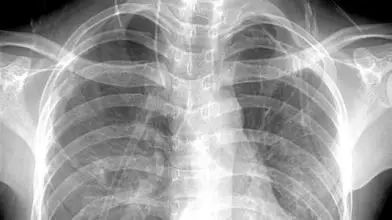

3、胸部——粗看X光片,细看CT

X光胸片可粗略检查心脏、主动脉、肺、胸膜、肋骨等,可以检查有无肺纹理增多、肺部钙化点、主动脉结钙化等。

胸部CT检查显示出的结构更清晰,对胸部病变检出敏感性和显示病变的准确性均优于常规X光胸片,特别是对于早期肺癌确诊有决定性意义。但是CT检查的辐射剂量高于X光。核磁对于肺部疾病的诊断,应用非常有限。